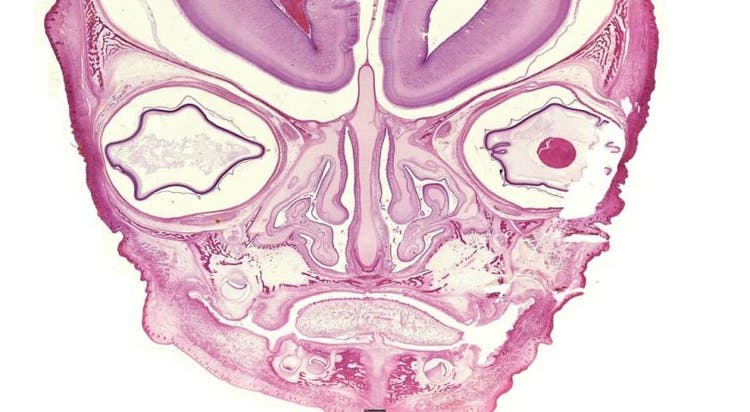

Dieses Bild mag zwar wie ein Gesicht mit zwei Augen, einer Nase und einem Mund aussehen, tatsächlich handelt es sich aber um die mikroskopische Aufnahme eines sich entwickelnden Knochens!